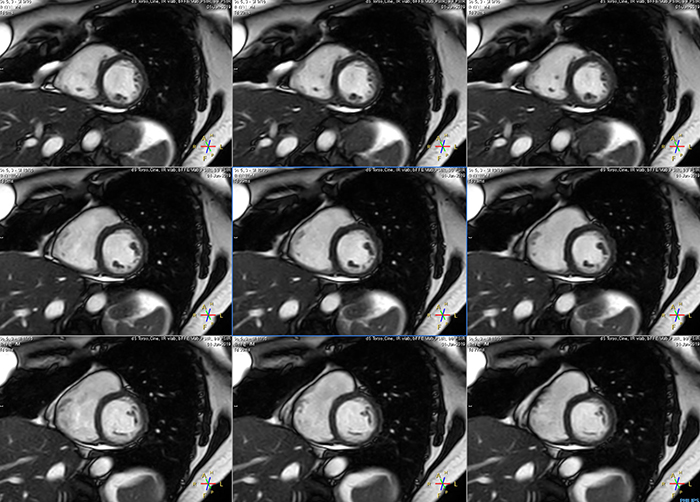

These are some images of a cardiac cine scan with a short breath-hold time. A high temporal resolution provides a smooth cine, which helps in assessing heart function. Ingenia Ambition.

Avila says that Compressed SENSE allows them to reduce breathhold time to 3 to 4 seconds in cardiac cine scans. “At the same time, we can now – based on cardiac frequency – obtain as many as 30 to 40 cardiac phases without sacrificing resolution, while before Ingenia Ambition, we were acquiring only 20 phases.

“This ability to use Compressed SENSE for obtaining higher temporal resolution translates to a much smoother cine. This allows me to better assess heart function,” Dr. Peña says.

The images obtained with Ingenia Ambition show large coverage and high uniform signal. More vessels are visible than in a previous exam of the same patient on Achieva. The movies show a higher temporal resolution in the Ambition acquisition than in a previous Achieva 1.5T exam. Both exams use a FOV of 300 mm and voxel height and width of 0.78 mm.

Achieva 1.5T

2:30 min. TE 1 ms, TR 4 ms

Ingenia Ambition

4D Trak XD 1:54 min. TE 1ms, TR 3ms

The team at Miami Cardiac & Vascular Institute also appreciates Ingenia Ambition’s capabilities for fast dynamic CE-MRA. “With 4D TRAK XD, we get much better temporal and spatial resolution. Previously, with the Achieva we needed 6 seconds per dynamic, but now we can shorten that to 2 seconds per dynamic,” Avila says. “As a result, we can see the transition from arterial to venous phase with much higher temporal resolution. This is important, for example, for imaging arteriovenous malformations, which are quite vascular.”

“On our previous system we really had to sacrifice image resolution to get to 5- or 6-second temporal resolution, while now – using 4D TRAK XD on Ambition – we no longer have to sacrifice image quality,” Dr. Peña says.